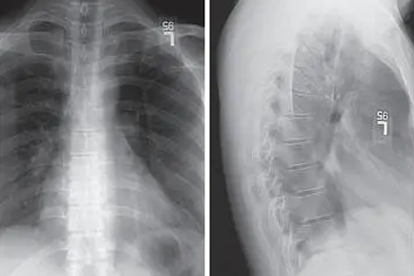

胸椎里边疼是怎么回事

胸椎里边疼可能由肌肉劳损、胸椎小关节紊乱、骨质疏松、胸椎间盘突出、强直性脊柱炎等原因引起,可通过休息理疗、药物镇痛、物理治疗、手术治疗等方式缓解。1、肌肉劳损 长期保持不良姿势或过度负重可能导致胸椎